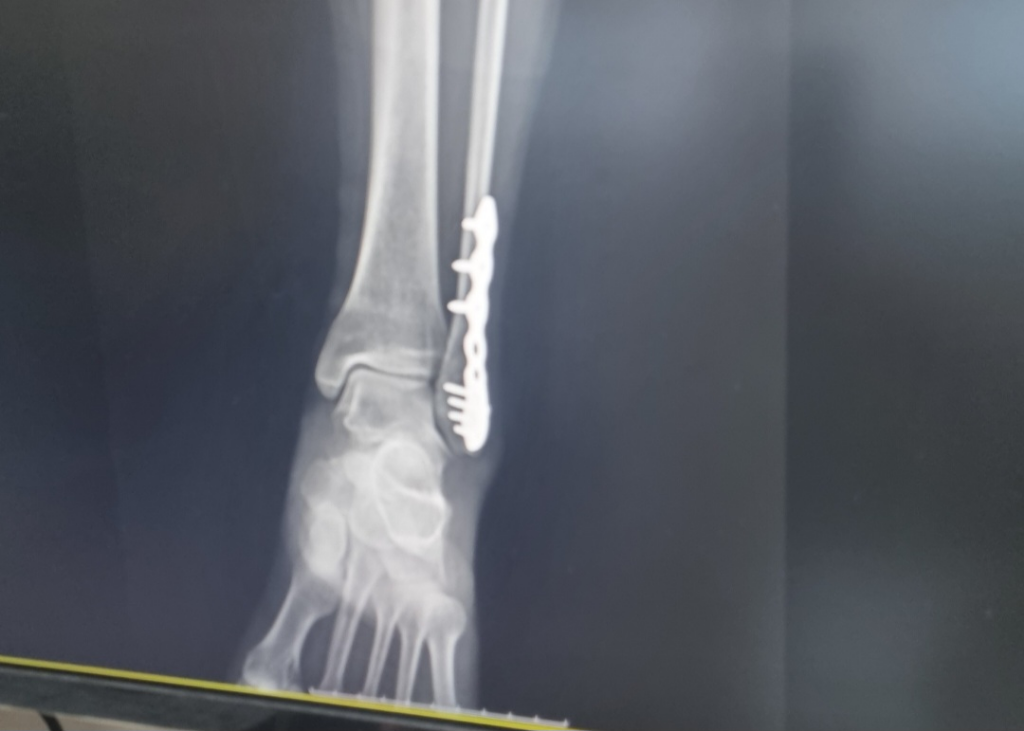

두 번째, 세 번째 사진은 플레이트를 심은 후의

사진입니다.

• 3번 째 사진

네 저정도의 틈은 신경쓸건 아닙니다.

이미 부러진부분을 그림처럼 딱 맞출순 거의 없습니다..